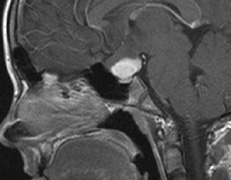

Fig. 17. Images from a 13-year-old boy with Von Hippel-Lindau syndrome. (a) Coronal postcontrast T1-weighted imaging reveals a cystic lesion with an enhancing nodule at the pial surface typical of a hemangioblastoma. (b) A second solid enhancing hemangioblastoma is seen at the craniocervial junction on a sagittal postcontrast T1-weighted image. (c) Associated cystic lesions (arrows) are seen within the pancreas.

Pancreatic lesions may be nonsecretory (most commonly cysts or cystadenomas) or secretory (islet cell tumor).179 In one study of 52 patients, 56% (29 patients) were found to have pancreatic lesions. The majority (19 of 29) had cystic changes only (Fig. 17C). Pancreatic lesions were the only abdominal manifestation of disease in 6 of 52 patients.180 In a separate study, pancreatic cysts did not show significant progression on follow-up examinations over an average period of 5 years.181 Like pancreatic cysts, islet cell tumors appear to be frequently asymptomatic.182